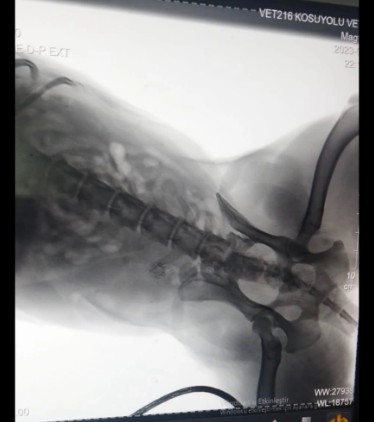

Kurşunun köpeğin omuriliğine isabet ettiği belirlendi. Köpeğin sağlık durumunun ciddiyetini koruduğu öğrenilirken, mahalle sakinleri polise giderek şikayetçi oldu.

Mahalle sakini Ela Durmazer ise, "Bu olay gerçekten çok üzücü. Bunun gibi birçok vaka var. Hayvan çok kötüydü. Omuriliğine saplanmış bir kurşun var. Şu an hayvan ameliyata da alınamıyor çünkü çok riskli bir ameliyat. Vücudunun güçlendirilmesi için mücadele ediyoruz. Bizim amacımız böyle şeylerin yapılmaması. Hiçbir koşulda hiçbir canlıya silahla ateş edilmemesi gerektiğini artık lütfen herkes duysun. Hiçbir canlıya bu yapılmayacak. Ve yapılmaması için tutanağı ben tutturdum. En azından hukuki sürecin başında olacağız" diye konuştu.